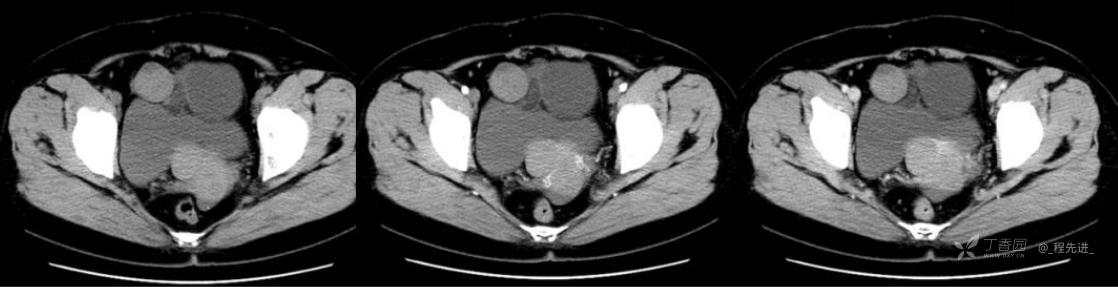

1月特别精彩病例|中老年女性,盆腔包块近半年持续增大【病理已公布】

患者年龄:53岁

简要病史:4年前体检时发现盆腔包块及子宫肌瘤,近半年复查盆腔彩超发现包块持续增大,近1年月经欠规律,伴腰、腹胀。

体格检查:宫颈举痛(+),子宫增大,质地中等,活动可,无压痛;右下腹轻压痛,无反跳痛,左侧附件区未扪及明显包块,无压痛。

阴式彩超:子宫约65*58*44mm大小,子宫肌层可见多个低回声块影,较大的为35*27mm(位于子宫前壁下段偏右侧壁),边界清,内回声欠均匀,后方回声衰减。考虑子宫多发肌瘤。子宫后壁可见一混合回声包块,大小约31*20mm,边界不清,内呈强弱回声,分布不均,考虑子宫腺肌瘤,其他疾患待删。子宫内膜厚6mm,宫颈可见多个囊性暗区,边界清,内透声好,后壁效应增强,较大的为15*11mm。子宫前方偏左侧可探及一大小89*75mm囊性肿块,边界清,壁薄光滑,内透声好,可见分隔光带